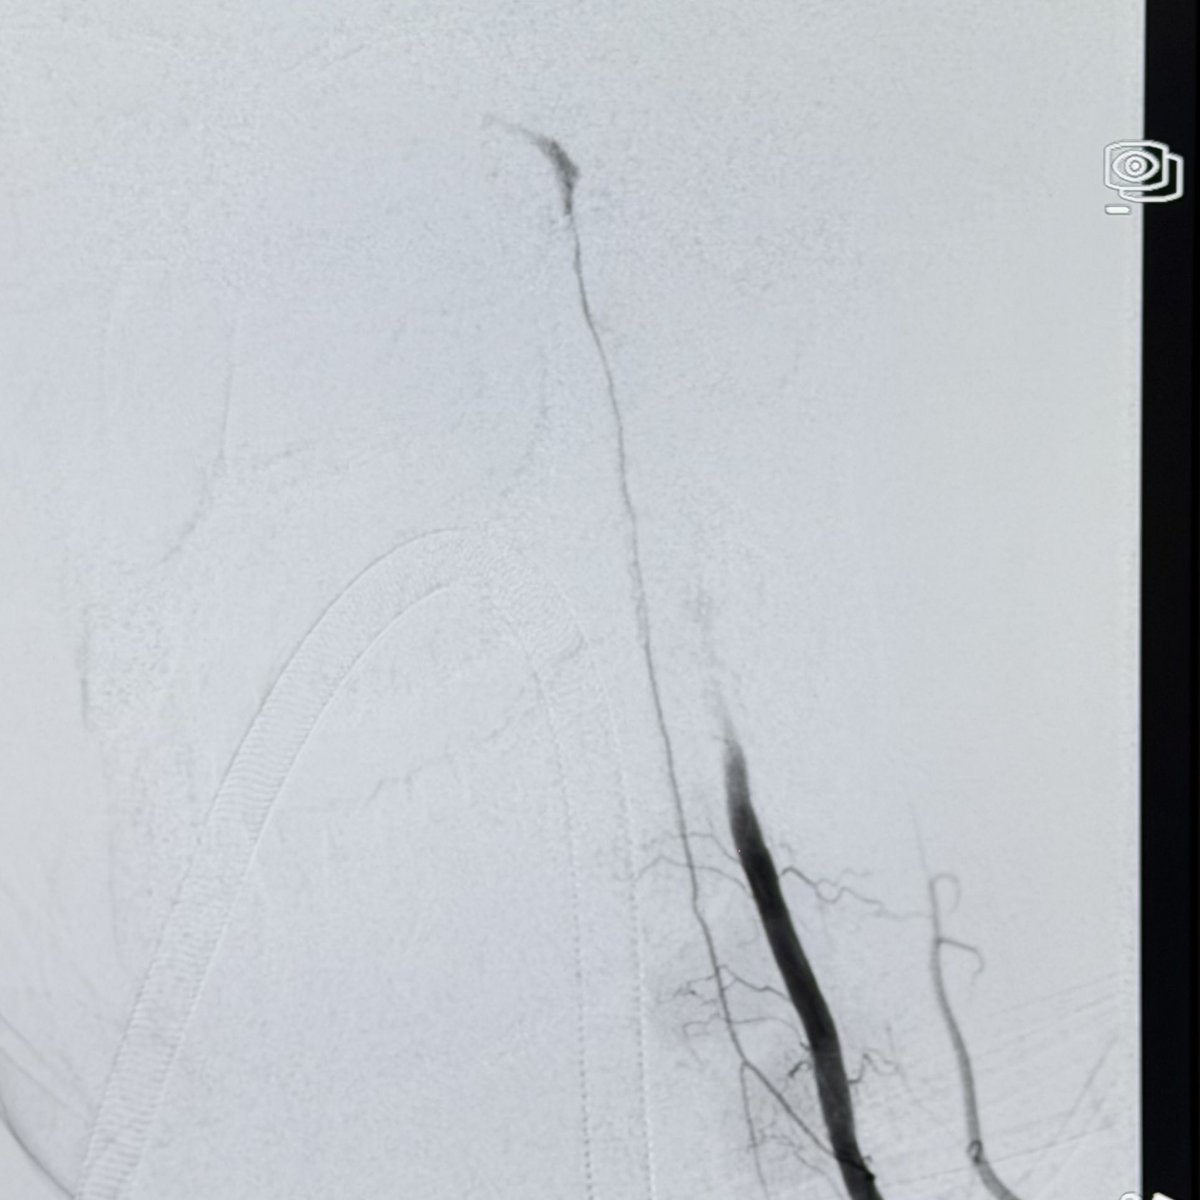

This 🧔♂️ presents with a subarachnoid haemorrhage in the left suprasellar cistern

DSA shows an infundibulum/ aneurysm of the left PCom. To coil or not was a conundrum. Every expert has a different take

The size is 3.4 mm x 2.6 and it is located in the region of the bleed.